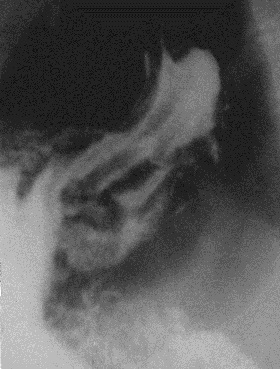

Ограниченное увеличение тени, обусловленное язвой, называется «ниша». Если ниша выходит на контур органа (рис. 13), то она имеет вид выступа треугольной или неправильной формы (1). Выше и ниже ниши часто определяется вогнутое вдавление – симптом „язвенного вала” (2). Морфологически в основе его - спазм стенки около язвы, отек слизистой оболочки и рубцовые изменения. За счет наличия язвенного вала создается впечатление большей глубины ниши. Если ниша не выходит на контур, то она определяется в виде контрастного пятна на слизистой оболочке – «ниша на рельефе» (рис. 14). Язвенный вал в подобных случаях представлен кольцевидным дефектом рельефа вокруг бариевого пятна. Язвы чаще определяются в желудке и луковице 12-перстной кишки.

Рис. 13. Рентгенограмма желудка в прямой проекции в вертикальном положении больного. В нижней трети тела по малой кривизне определяется ниша (описание в тексте). Язвенная болезнь желудка.

В средней трети тела желудка на фоне рельефа слизистой оболочки определяется бариевое пятно. Вокруг – дефект наполнения, обусловленный язвенным валом. Язвенная болезнь желудка.